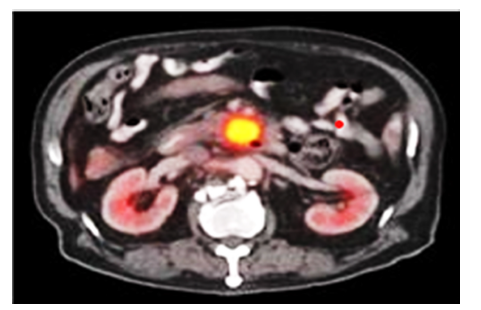

Positron Emission Tomography–CT (PET-CT) detects metabolic activity using 18F-FDG, identifying malignant lesions before structural changes are visible. It is particularly useful for staging and detecting distant metastases [4]. Axial PET/CT scan demonstrating a hypermetabolic lesion in the pancreatic region in Figure 5 below, consistent with suspected pancreatic adenocarcinoma. The lesion exhibits intense 18F-FDG uptake, indicative of elevated metabolic activity. Bilateral kidneys are visualized with physiologic tracer excretion. A smaller adjacent focus suggests possible regional lymphatic involvement. These findings support further diagnostic evaluation via endoscopic ultrasound and tissue biopsy.

Figure 5:MRI scan of pancreatic tumour. Source: Jha and Bijan [4].